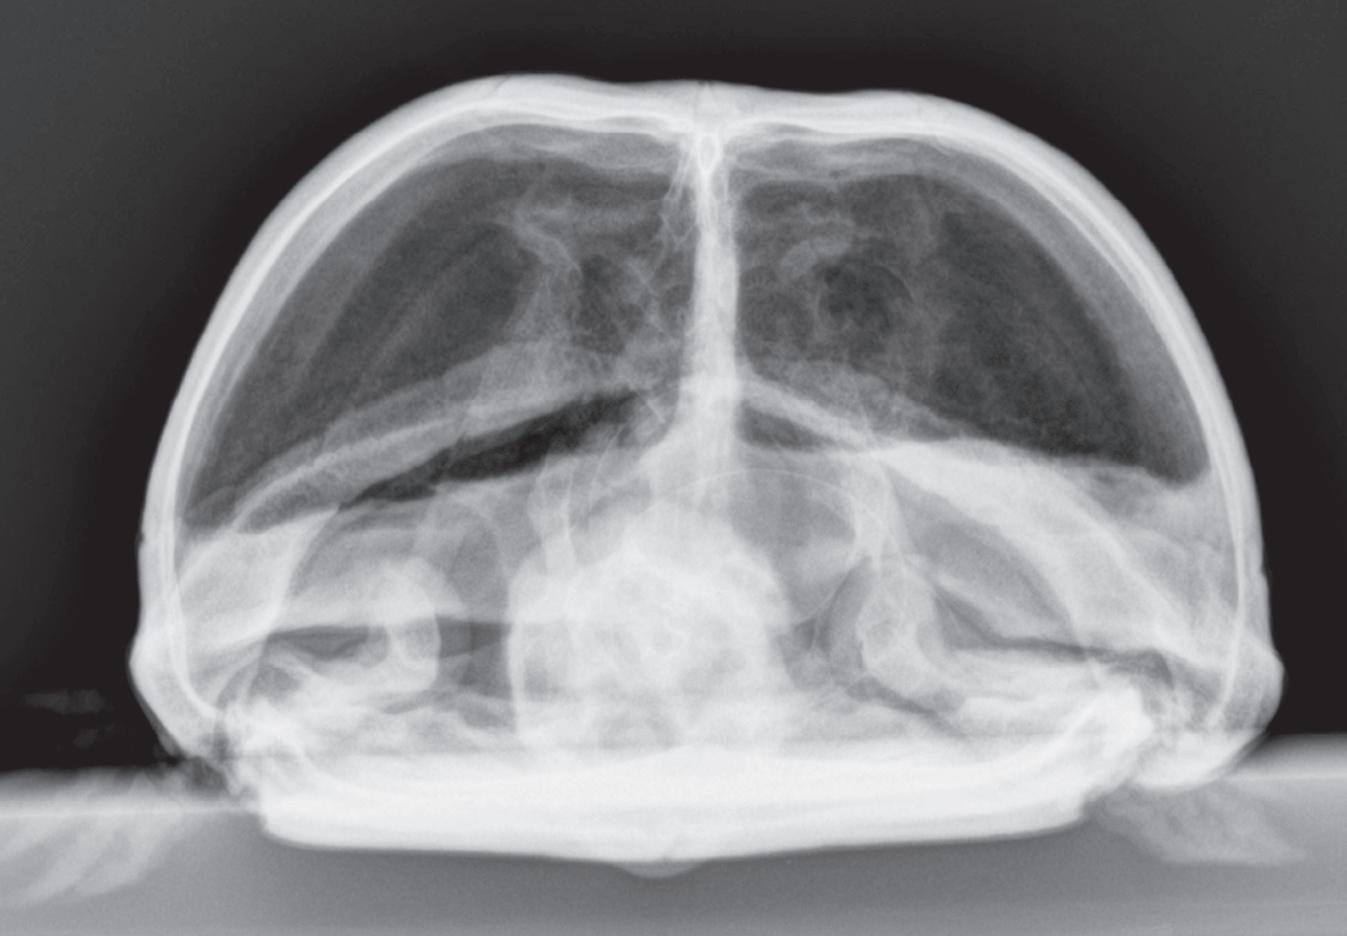

Figure 1-6. Dorsoventral (A), lateral (B), and rostrocaudal (C) radiographs of a box turtle. In A and B, which are orthogonal to each other, it is clear that the subject is a turtle. Eggs are visible in the coelom. In C, which is also an orthogonal view with respect to both A and B, it is not obvious that the subject is a turtle because this orientation is uncommon and unfamiliar. The eggs are also not visible in C.